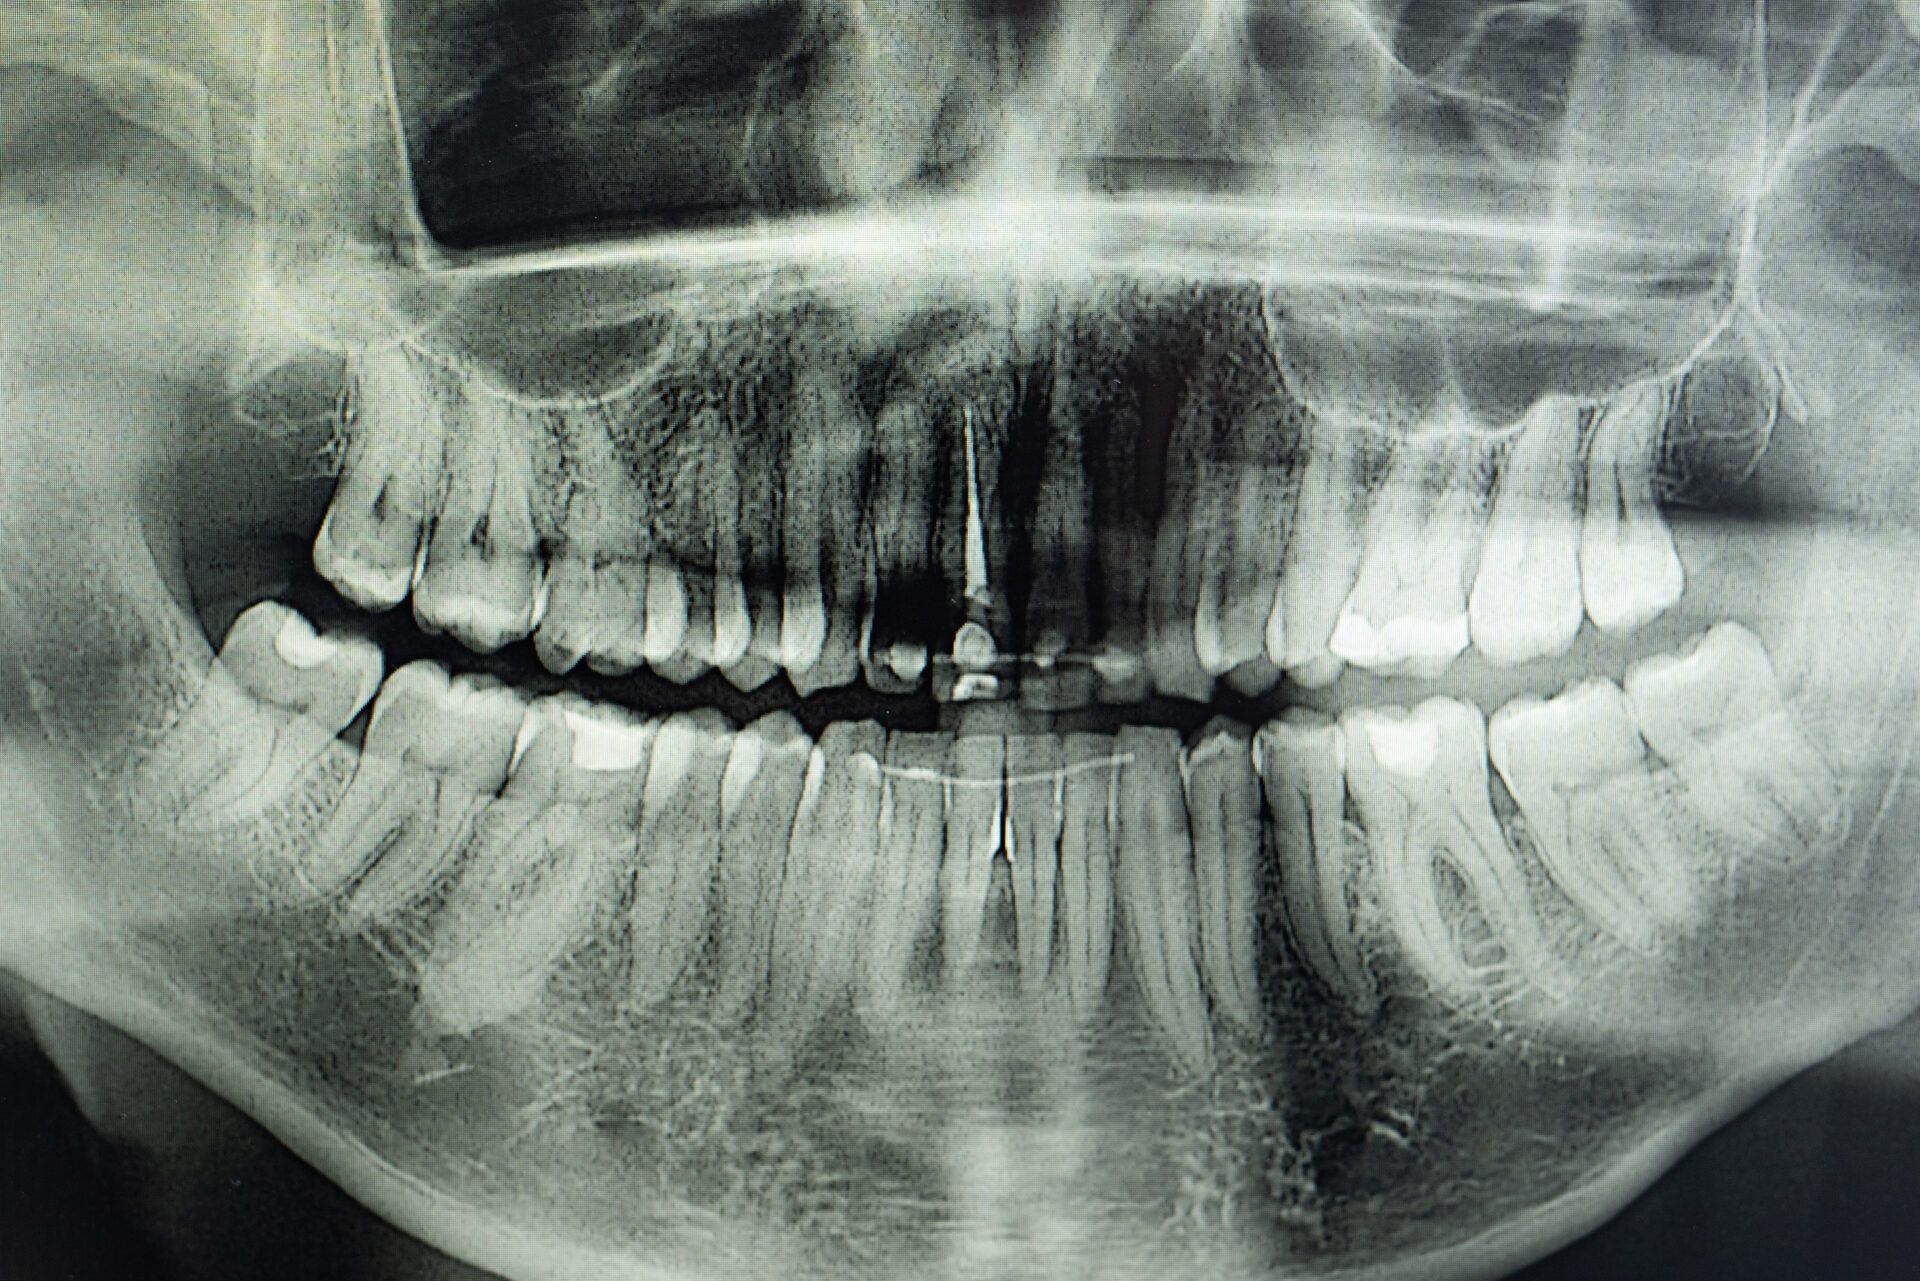

Digital x-ray - impacted wisdom teeth removal East Melbourne - East Melbourne dentist

What is the problem with Wisdom Teeth? Since they’re last to erupt, there may not be enough room in the jaw for the erupting wisdom teeth. This may stall their eruption and make brushing and flossing these teeth difficult. Food and bacteria often become trapped between the wisdom tooth and its neighbouring molar tooth, which…